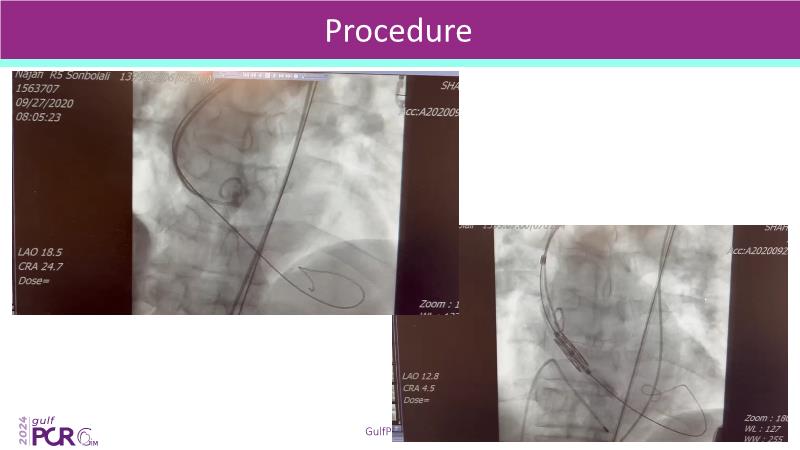

Stay ahead in TAVI innovation by exploring the advanced balloon-expandable Myval THV series. This session highlights the latest clinical data, optimal sizing and implantation techniques, and valuable real-world insights, including long-term follow-up results.

- To learn about the novel balloon expandable Myval THV series and the up-to-date clinical evidence for it

- To understand the best practices for Myval sizing and implantation technique for best outcomes